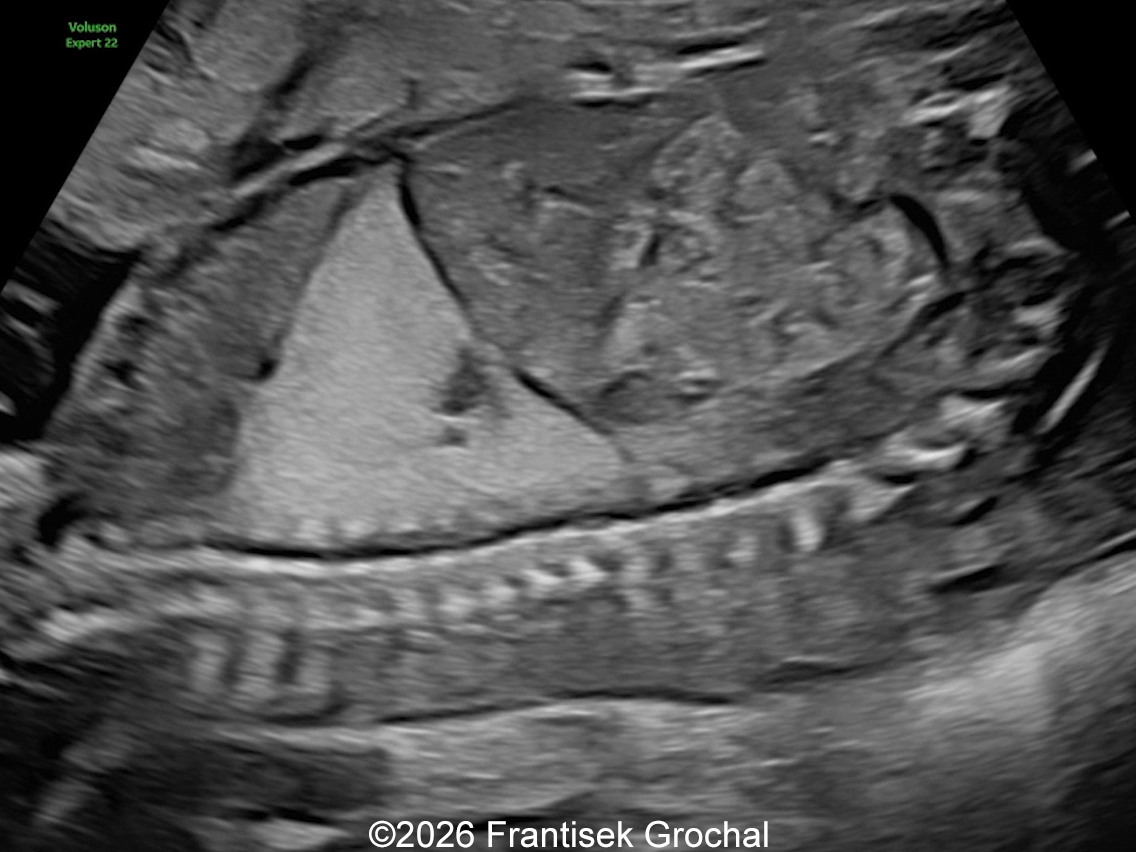

22+3 weeks of gestation – sagittal view demonstrating a well-circumscribed, triangular pulmonary sequestration.

Image 1 22+3 weeks of gestation – sagittal view demonstrating a well-circumscribed, triangular pulmonary sequestration.